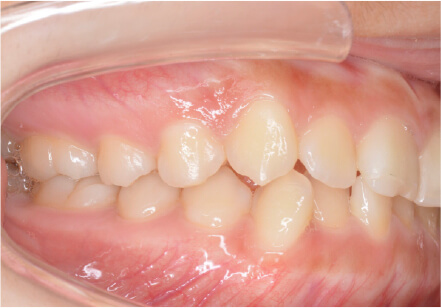

9歳

/

男性

相談内容

下の歯が重なっている。

カウンセリング・診断結果

myoからの移行

治療内容・方法

全額アライナー矯正

術後の経過・現在の様子

上下3〜3fix使用

治療のリスク

痛み・歯根吸収・歯肉退縮・虫歯・後戻り

費用・治療期間

880,000円、1年2ヶ月

トレーニングなど